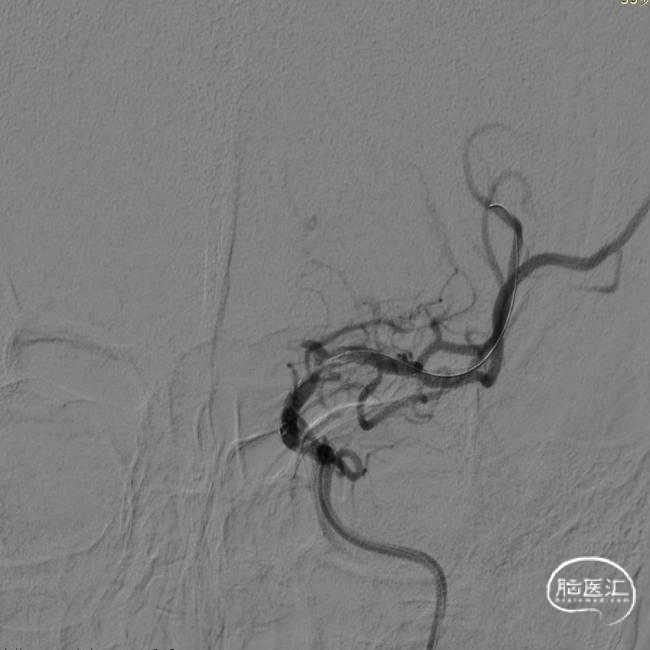

L-ICA工作位

责任血管为左侧颈内动脉C7段,提示重度狭窄(95%),左侧大脑中动脉上干(额支)可见低灌注所致显影不连续。结合患者目前的运动性失语表现,考虑此次脑梗死的分型为大动脉粥样硬化型,动脉-动脉栓塞合并低灌注栓子清除率下降的混合机制。事不宜迟,与患者家属再次沟通病情及下一步的手术建议,拟行右侧颈内动脉C7段球囊扩张成型术备支架置入成型术。老张的老婆还是很爱老张的,很快签字同意了手术方案。